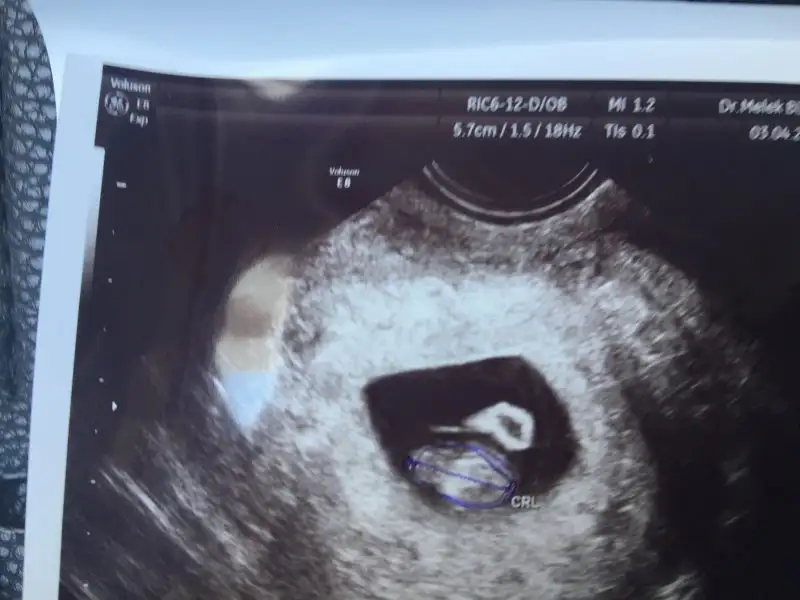

Birde benm şçin tahmin de bulunurmusunuz lütfen Vajinal ultrason la bakıldı bugün

Eklentiler

• IMG_3928.webp

20,3 KB · Görüntüleme: 199